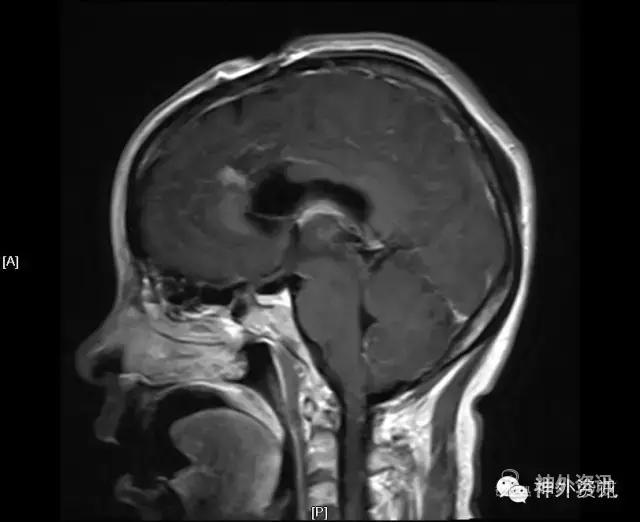

CT头胸部平扫:右丘脑占位,考虑胶质瘤可能,建议进一步检查。左侧基底节区腔梗右下肺感染;左肺上叶舌段异常改变,考虑为畸形血管可能,必要时增强检查两侧胸腔少量积液。

MRI:右侧丘脑占位,考虑胶质瘤可能性大(Ⅲ-Ⅳ级),病灶累及中脑右侧大脑脚,轻度脑积水;不除外转移瘤可能,请结合相关病史及检查。

初步诊断:丘脑占位,胶质瘤可能。

影像学检查: